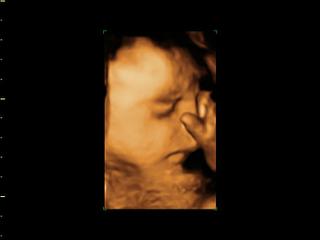

Ahojte kočky,sme doma zo 4D-tak malinký riadne vystrájal-aj sa pousmieval na nás-prekrásny pohľad.Doktor nám povedal,že Paťko je už hotové,vyzreté bábätko a že keby náhodou sa mal teraz narodiť,že vôbec nemusím mať oňho obavy,lebo už je už všetko ako má byť!Dokonca mi praje,aby sa narodil trošičku skôr,lebo ozaj je väčší...

@lianka7 odpadnem je kraaasny!!! Vidis mala som pravdu, ze sa este aj usmeje na maminku 🙂 to je tak uzasna sprava, ze uz je pripraveny a vporiadku urcite sa velmi tesis to je ta naj sprava pre vsetky maminky.

@veronika1417 samozrejme,az mi slzicky vysli od stastia...vidiet spokojne usmiate babatko a este ked lekar potvrdi,ze je pripravene a krasne vyzrete...pekne sme sa s drobcekom rozlucili na 4D 😉